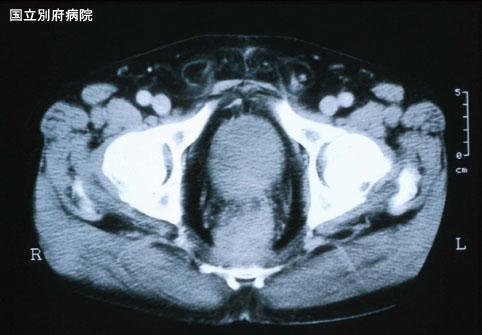

症例提示(所在地,施設名等): 大分県・ 別府医療センター

疾患(病理主体)の分類悪性黒色腫/

部位(臓器別)大腸/直腸

検査方法CT

腫瘍の肉眼分類1型(腫瘤型)/

病変の最大径(ミリ)40以上

腫瘍の深達度ss(a1)